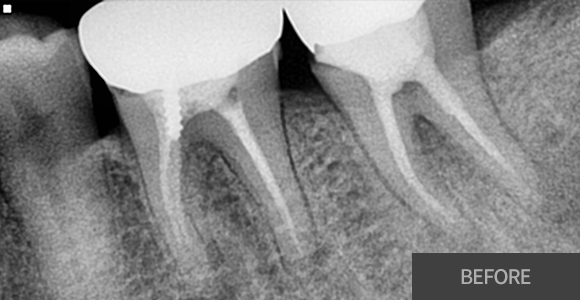

잇몸치료

잇몸치료가 전공 분야인 치주과 원장님께서

꼼꼼하고 꾸준하게 잇몸을 관리해드리고 있습니다.

대학병원에서 주로 시행하는 잇몸 수술까지도 가능한

전문의 원장님과 꾸준한 잇몸관리를 받으시길

바랍니다.